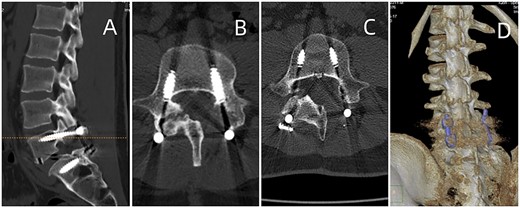

CT showed erosions in the facet joints over left L5-S1, with soft tissue masses and sclerotic margins (Fig. 1). MRI depicted a 1.8◊1.1 cm extra-dural mass in the left L5-S1 facet joints, displaying low signal on T1-weighted and high signal on T2-weighted imaging. Gadolinium contrast highlighted heterogeneous enhancement of the lesion (Fig. 2).

(A) Sagittal CT displaying lumbar spondylolysis at L5. (B) Axial CT revealing articular subchondral erosions and soft tissue masses at the left facet joint L5-S1. (C) Coronal CT and (D) 3D image demonstrating articular erosions and punched-out lesions of L5-S1, along with spondylolysis at L5.